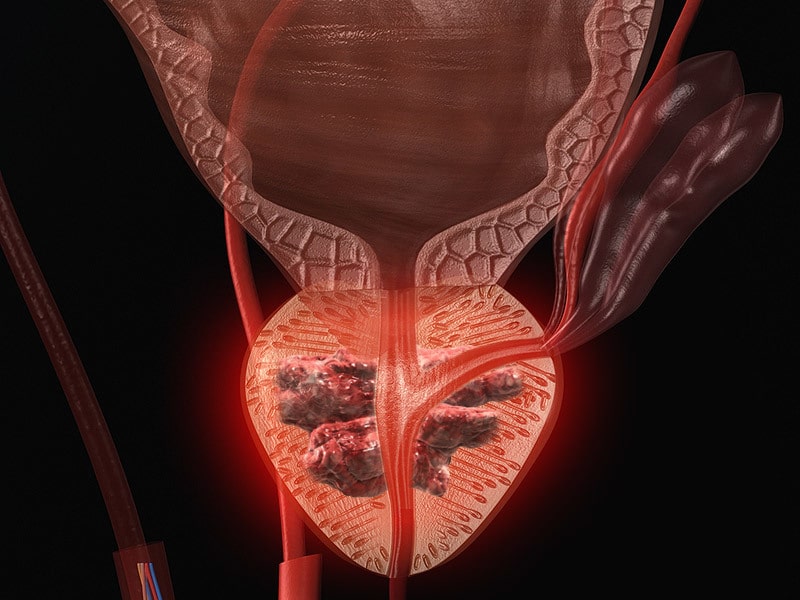

نقش تستوسترون در رشد و پیشرفت سرطان پروستات و ایمنی روش TThبعد از درمان سرطان پروستات ویا نقش ان در برقراری کنترل موثر هنوز مورد بحث است.نگرانی های متعددی در استفاده از TTh در مردان وجود دارد, به ویژه برای انهایی که سابقه سرطان پروستات دارند که شامل افزایش خطر بیماری های قلبی عروقی تا پیشرفت و یا بازگشت سرطان می شود.درحالیکه بیشتر بیماران سرطان پروستات نسبت به گذشته عمر طولانی تری دارند کاهش و یا عدم ترشح هورمون که یکی از عوارض جانبی قابل ملاحضه است باید دقت بیشتری در تصمیم به روش درمان TTh گرفته شود .در این مقاله منابع تاثیر تستوسترون بر پروستات و همچنین تاثیر و ایمنی تستوسترون خارجی (exogenous)در مردان با سابقه سرطان پروستات مورد بررسی قرار گرفته است.

تحقیقات اخیر نشان می دهد که بهبود کیفیت زندگی با TTh کاملا مطالعه و شناخته شده است , در حالی که بحث ها در مورد افزایش قابل توجه خطر سرطان و سایر تاثیرات ناخوشایند کاملا کم اهمیت است. افزایش شمار سرطان پروستات , بازگشت سرطان و یا خطر بیماری های قلبی و عروقی هیچ کدام ثابت نشده است.در مردان با خطر بالای سرطان پروستات مستندات برای کاهش TTh خیلی محدود است و TTh باید با احتیاط استفاده شود.به نظر نمی رسد با داده های فعلی ترس از TTh برای ایجاد یا بدتر کردن سرطان پروستات قابل اعتماد باشد.اگرچه مطالعات بیشتری برای تعیین ایمنی TTh در مردان مبتلا به سرطان پروستات لازم است توجه بیشتری باید به معالجه مردان hypogonadal با سابقه CAP داشت.